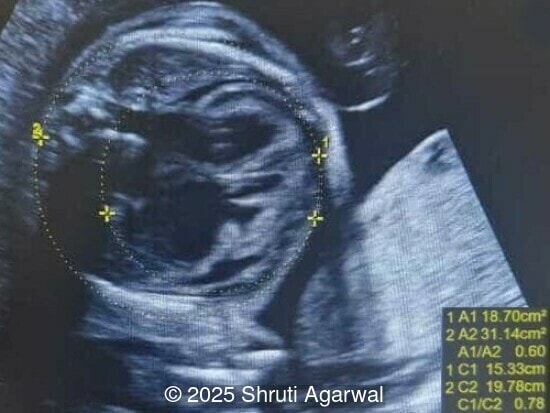

- Image 3: Cardiomegaly

Chorangiomas greater than 5cm are referred to as a giant chorangioma and occur in approximately 1 in 2,700 pregnancies [2]. Giant chorangioma can be clinically significant, causing various fetomaternal complications. In a study reviewing 175 cases of chorangioma, approximately 34% of giant chorangiomas experienced complications [2]. Arteriovenous shunting in giant chorangioma can increase venous return to the fetal heart, causing hypervolemia, tachycardia, and cardiomegaly, leading to heart failure, hydrops fetalis, and fetal demise. Large lesions can also divert nutrients and oxygen from the fetus, manifesting as growth restriction. Placentomegaly occurs due to a hyperdynamic circulation as a result of arteriovenous shunting. In such cases, fetus may suffer from anemia and thrombocytopenia due to sequestration of red blood cells and platelets by the tumor. Polyhydramnios can occur due to both direct transudation into the amniotic fluid and to fetal polyuria secondary to the hyperdynamic circulation. Additionally, preterm delivery and maternal mirror syndrome with generalized fluid overload and preeclampsia can occur with giant chorangiomas [2,8].

Prenatal diagnosis depends on ultrasound, however, chorangioma can cause an increase in maternal serum alpha-fetoprotein [3]. Ultrasound examination reveals a hypo- or hyperechoic, well-circumscribed mass, which is usually located underneath the chorionic plate near the umbilical cord insertion, and often protrudes into the amniotic cavity. Color Doppler demonstrates large vascular channels around and within the tumor [6,9]. In cases of giant chorangiomas, echocardiography should be performed to assess cardiac function and measure fetal middle cerebral artery peak systolic velocity for diagnosis of fetal anemia. Regular ultrasounds with Doppler studies are used to monitor tumor size, fetal growth, amniotic fluid volume, and signs of fetal anemia or heart failure. The frequency of exams is based on tumor size and associated complications. With small tumors, assessment may occur every 3-4 weeks, whereas in large tumors, the ultrasound scan may be done every 1-2 weeks [3]. These regular assessments can diagnose conditions that require intervention, such as polyhydramnios, hydrops, or hemolytic anemia.